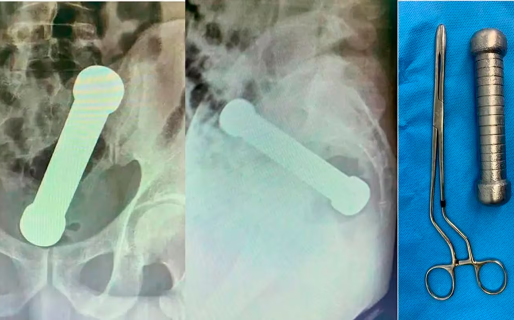

En abril de 2022, un ciudadano brasileño tuvo que ser internado de urgencia tras un peligroso juego sexual y debieron operarlo para extraerle una mancuerna. Sin embargo, la historia generó revuelo en su momento y en los últimos días volvió a viralizarse en las redes sociales por las impactantes imágenes de las radiografías.

En aquel momento, la víctima, de 54 años, se presentó en un hospital de la ciudad Manaos, noroeste de Brasil, con dolor abdominal, náuseas y dificultad para defecar. Le hicieron una radiografía que mostró que tenía un objeto de metal de 4,4 libras y casi 20 cm en el ano.

En ese entonces, los médicos revelaron que se trataba de una práctica sexual. Afirmaron que tuvieron que actuar rápido para evitar una perforación anal u otra lesión grave, según informó TN.

En primera instancia, los cirujanos intentaron extraerle el objeto usando pinzas, pero finalmente tuvieron que intervenirlo. La operación fue exitosa y fue dado de alta después de tres días sin complicaciones.